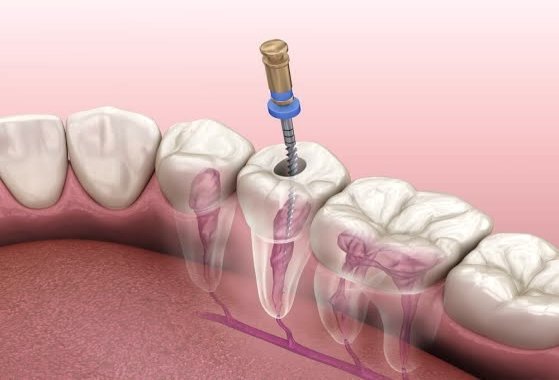

Видалення нерва зуба: коли, як і чому це потрібно робити

Здорові зуби — це не лише гарна усмішка, а й важлива умова нормального функціонування всього організму. Однією з найпоширеніших стоматологічних процедур є видалення зубного нерва, або депульпація. Для багатьох пацієнтів саме слово «видалення нерва із зуба» звучить тривожно, адже асоціюється з болем та складним лікуванням. Проте сучасна стоматологія пропонує методики, які дозволяють провести цю процедуру…